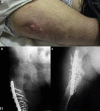

Osteogenesis imperfecta (OI) is a rare congenital disease characterized by alterations in bone quality, with susceptibility to fractures, instability, deformities, and osteoarthrosis. Prosthetic surgery in these patients is associated with an abnormally high rate of implant failures. On the other hand, abnormal bone fragility adds to the complexity of revision surgery in such individuals-thus representing a genuine challenge for the orthopaedic surgeon. We present a case of femoral reconstruction in a patient with OI and prosthetic loosening after reconstruction secondary to femoral septic pseudoarthrosis. Intramedullary total femoral reconstruction was carried out after exceeding the biological reconstruction limits. This is the first reported instance of the use of an intramedullary total femur arthroplasty as salvage technique in an OI patient. This technique should be considered when we have exceeded biological limits for femoral fixation.